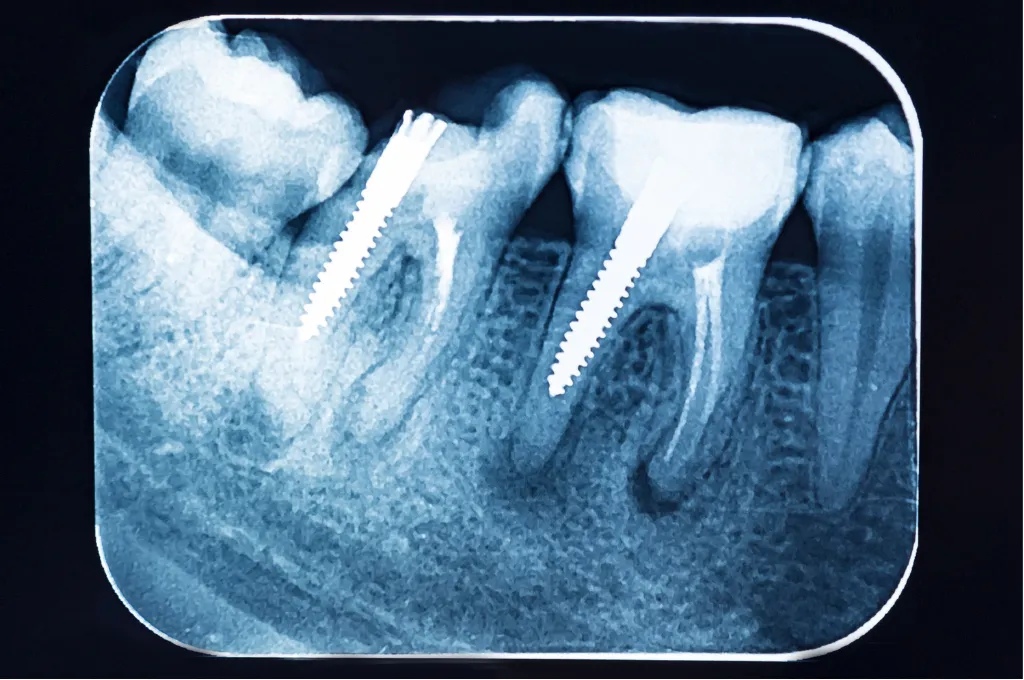

A dental X-ray is an imaging technique used to capture detailed views of your teeth, gums, and jawbone. These images help identify tooth decay, dental cavities, infections, impacted teeth, bone loss, and other dental conditions that may not be visible during a regular exam.

At Smile Scarsdale Family Dental, your trusted family dentists in Scarsdale, we use low-radiation digital X-rays that are safer, faster, and more environmentally friendly than traditional film X-rays. Our X-ray services include:

Bitewing X-Rays – Detect cavities between teeth.

Panoramic X-Rays – Provide a full view of the entire mouth, including the jawbone and sinuses.